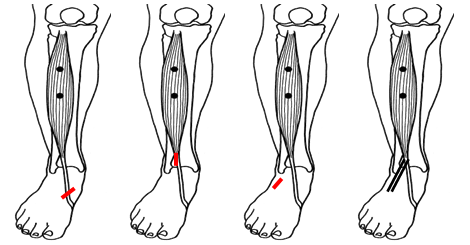

SPLATT (Split anterior tibial tendon transfer)

De SPLATT, of ½ tibialis anterior transpositie, omhelst het verplaatsen van de helft van de tibialis anteriorpees naar de buitenzijde van de voet. Hiermee wordt wederom een kracht van de binnenzijde naar de buitenzijde van de voet verplaatst om de balans te verbeteren. De verplaatste pees wordt meestal vastgehecht aan de peroneus tertiuspees die aan de voor-buitenzijde van de enkel/voet loopt en de voet naar buiten en omhoog beweegt.

Figuur 3: De tibialis anteriorspier. Bij het streepje op het linkerplaatje komt een litteken waar de helft van de pees wordt losgemaakt. Dat stukje pees “tunnelen” we naar net boven de enkel (2e plaatje). Dan verplaatsen we dat stukje pees naar de buitenzijde van de voet (streepje op 3e plaatje) en hechten deze vast aan de peroneus tertiuspees. Op het meest rechtse plaatje staat de eindsituatie waarbij de pees voor de helft naar de buitenzijde van de voet is verplaatst en de balans is veranderd.